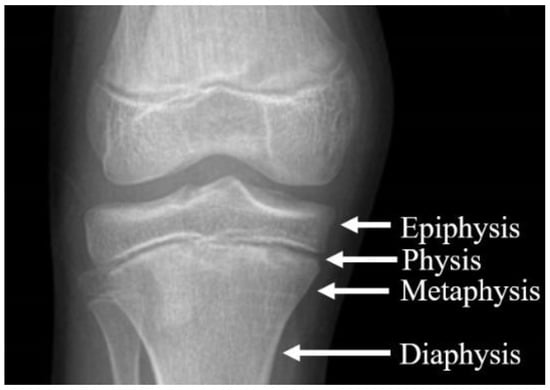

Epiphyseal stapling was introduced by Walter Blount in 1949, see [6], and since then, it has become a common procedure of correcting, in particular, angular deformities of the knee (genu varum or genu valgum) in children. The growth of the child’s or adolescent’s bone is associated mainly with physis, i.e., a cartilage structure near joints; see [1,4]. Blount staples are also used for pseudoarthrosis treatment [7].

Using staples, the physis (epiphyseal plate) can be relatively simply restrained either on both sides when correcting limb length discrepancy (i.e., “epiphysiodesis”) or only on one side when correcting angular deformities (i.e., “hemiepiphyseodesis”) (see Figure 1 and Figure 2). Unlike the irreversible method of permanent epiphysiodesis, see [8], epiphyseal stapling does not destroy the epiphyseal plate and, therefore, allows resumption of the growth once the optimal correction is achieved; see [4].

The bone growth occurs in the epiphyseal plate, where a new bone mass is created. Considering this fact, the simulation of the growing process turned out to be difficult. For this reason, we came up with a solution where the artificial bone (tibia) is cut in two at the position of the epiphyseal plate; furthermore, we assume that the bone grows predominantly in the direction of the bone axis (i.e., only oppositional growth is considered), which means that growth can be simulated by pulling the two bone segments away from each other.

Figure 1. Parts of the growing bone (tibia).